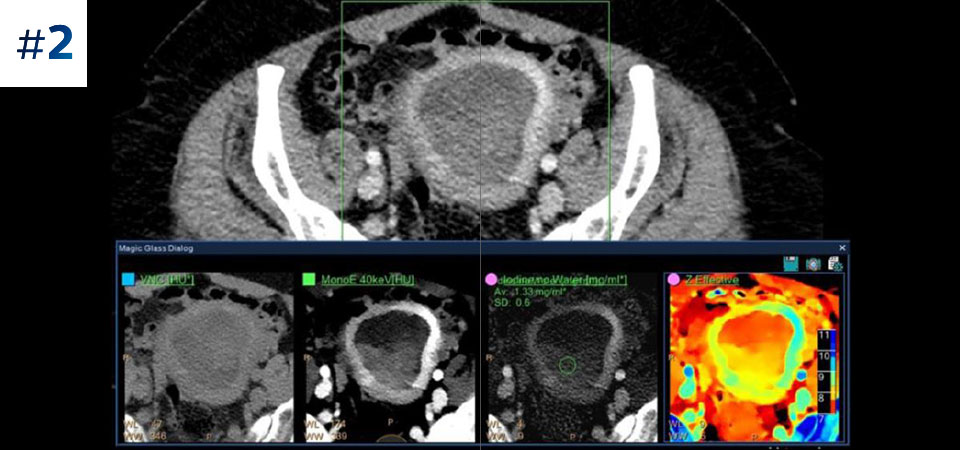

Брюшная полость/таз